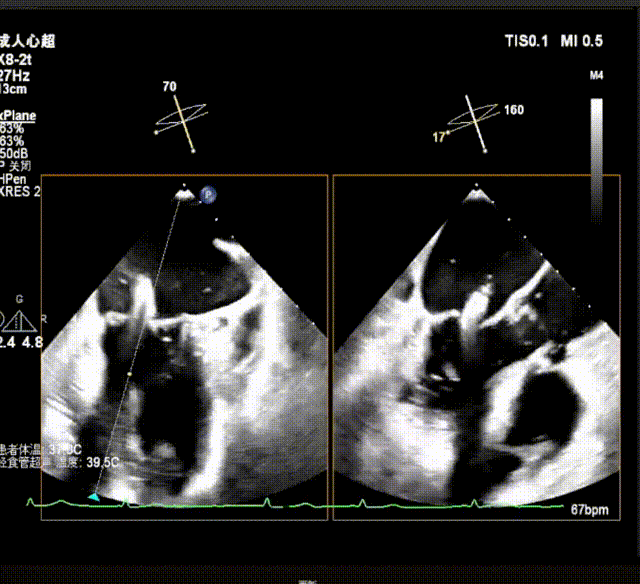

术前超声诊断

X-plane视窗可见二尖瓣瓣叶“连枷样”运动;

3D enface view示二尖瓣内后叶2偏1区瓣尖可见断裂的腱索呈“连枷样”运动,偏心性返流

PISA定量:EROA=1.06cm²,Rvol=145ml,Vmax=399cm/s

PW显示左肺静脉收缩期血流频谱呈逆向

3D模式测量二尖瓣瓣口面积5.62cm²术前TEE房间隔高度约4.72cm